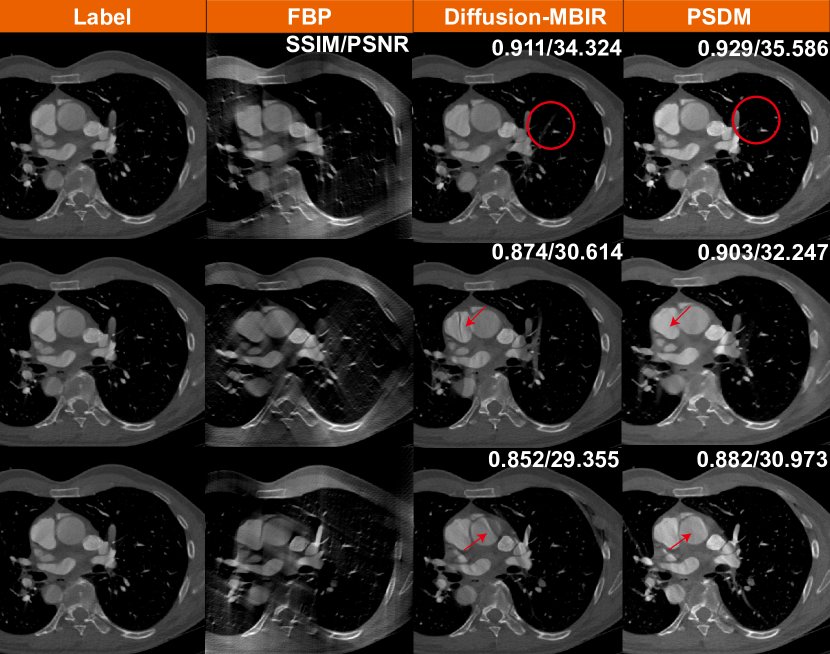

Refer to caption

Figure 5: Reconstruction results from the AIMI COCA dataset with 120 views using different methods. The display window is [900900-900 100010001000] HU.

Generalization is a major issue for DLR-based methods, especially for models requiring supervised learning. If a model is trained strictly on data with a specific angle range (e.g., 0–120°), it will not generalize well to other angular ranges. However, different clinical situations might require different angular ranges. For instance, certain anatomical regions or pathologies are better visualized with a specific angle range. To further demonstrate the advantages of PSDM, the algorithm is applied to a real clinical cardiac dataset. With the approval of the Institutional Review Board of the University of Massachusetts, Lowell, a deidentified clinical cardiac CT dataset is obtained from a GE HD 750 scanner. The patient was scanned using axial mode. 1,520 projections are acquired over an angular range of 556° (\approx 1.54 rotations). Each projection row has 835 elements at 1.095 mm pitch. The source to the rotation center distance is 538.5 mm, and the source to the detector distance is 946.7 mm. Reconstruction is performed by FBP using equi-angular geometry, where the image size is set to 512×512512512512\times 512 to accelerate the sampling process. Since the supervised learning-trained models (FBPConvNet and TomoGAN) usually can only process specific angle range, we compare only the two unsupervised learning methods: Diffusion-MBIR and PSDM. During the sampling stage, these two methods directly utilize the checkpoints trained on the aforementioned Stanford AIMI COCA datasets. Fig. 6 shows the 120-view limited-angle reconstruction images from different angular ranges. We find that both Diffusion-MBIR and PSDM produce consistent and apparently acceptable results. However, compared with the Diffusion-MBIR, the results produced by PSDM exhibit fewer limited-angle artifacts and appear to provide a more realistic representation. These differences can be seen in the areas and structures underscored by red circles and arrows. Specifically, in the atrial region denoted by the red arrow, PSDM produces more stable results, while Diffusion-MBIR still exhibits limited-angle artifacts in the atria.

Figure 6: Reconstruction results from a clinical cardiac CT scan, using different methods, each corresponding to different scanning angular ranges of 120°. The first row are reconstructions from spanning angles 0° to 120°, the second row are for 30° to 150°, and the third row are for 60° to 180°. The display window is [400400-400 150015001500] HU.